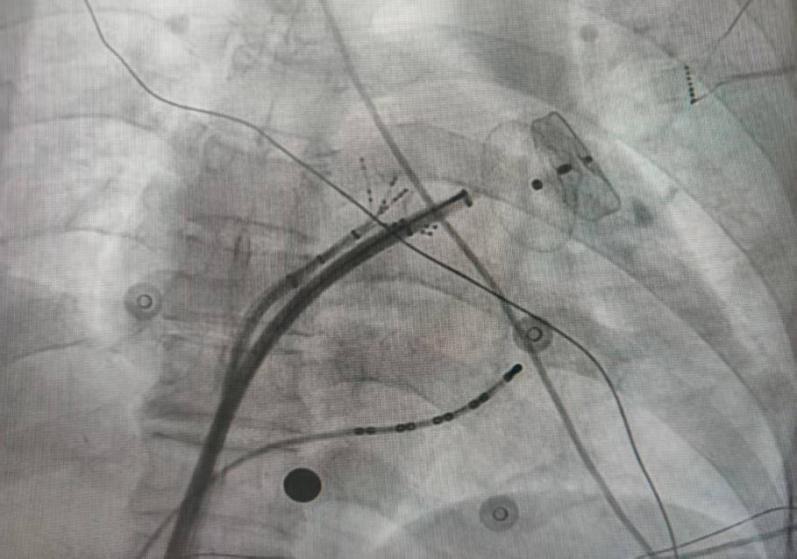

为进一步提高手术治疗效果,龚辉电生理团队决定采用革命性的新款智能温控超高功率消融导管进行房颤射频消融术,并联合左心耳封堵手术。手术由龚辉主任医师和彭飞主治医师完成,手术时间显著缩短,整体控制在2个半小时内,患者术中的疼痛感明显减轻,效果显著。

作为目前国际最先进的射频消融导管,QDOT MICRO导管功率高达90瓦,仅需4秒就可完成一个点的消融,大幅提升了手术效率,缩短手术时间。导管拥有6个温度感受器,可以时刻灵活控温,减少并发症发生率,从而提高消融效果。

此外,导管新增的3个微电极能够更精准地诊断复杂心律失常中的特殊电位。值得一提的是,导管还配有66个盐水灌注孔,提高了灌注效率,降低了心脏负荷,对心衰患者的房颤治疗尤其有益。